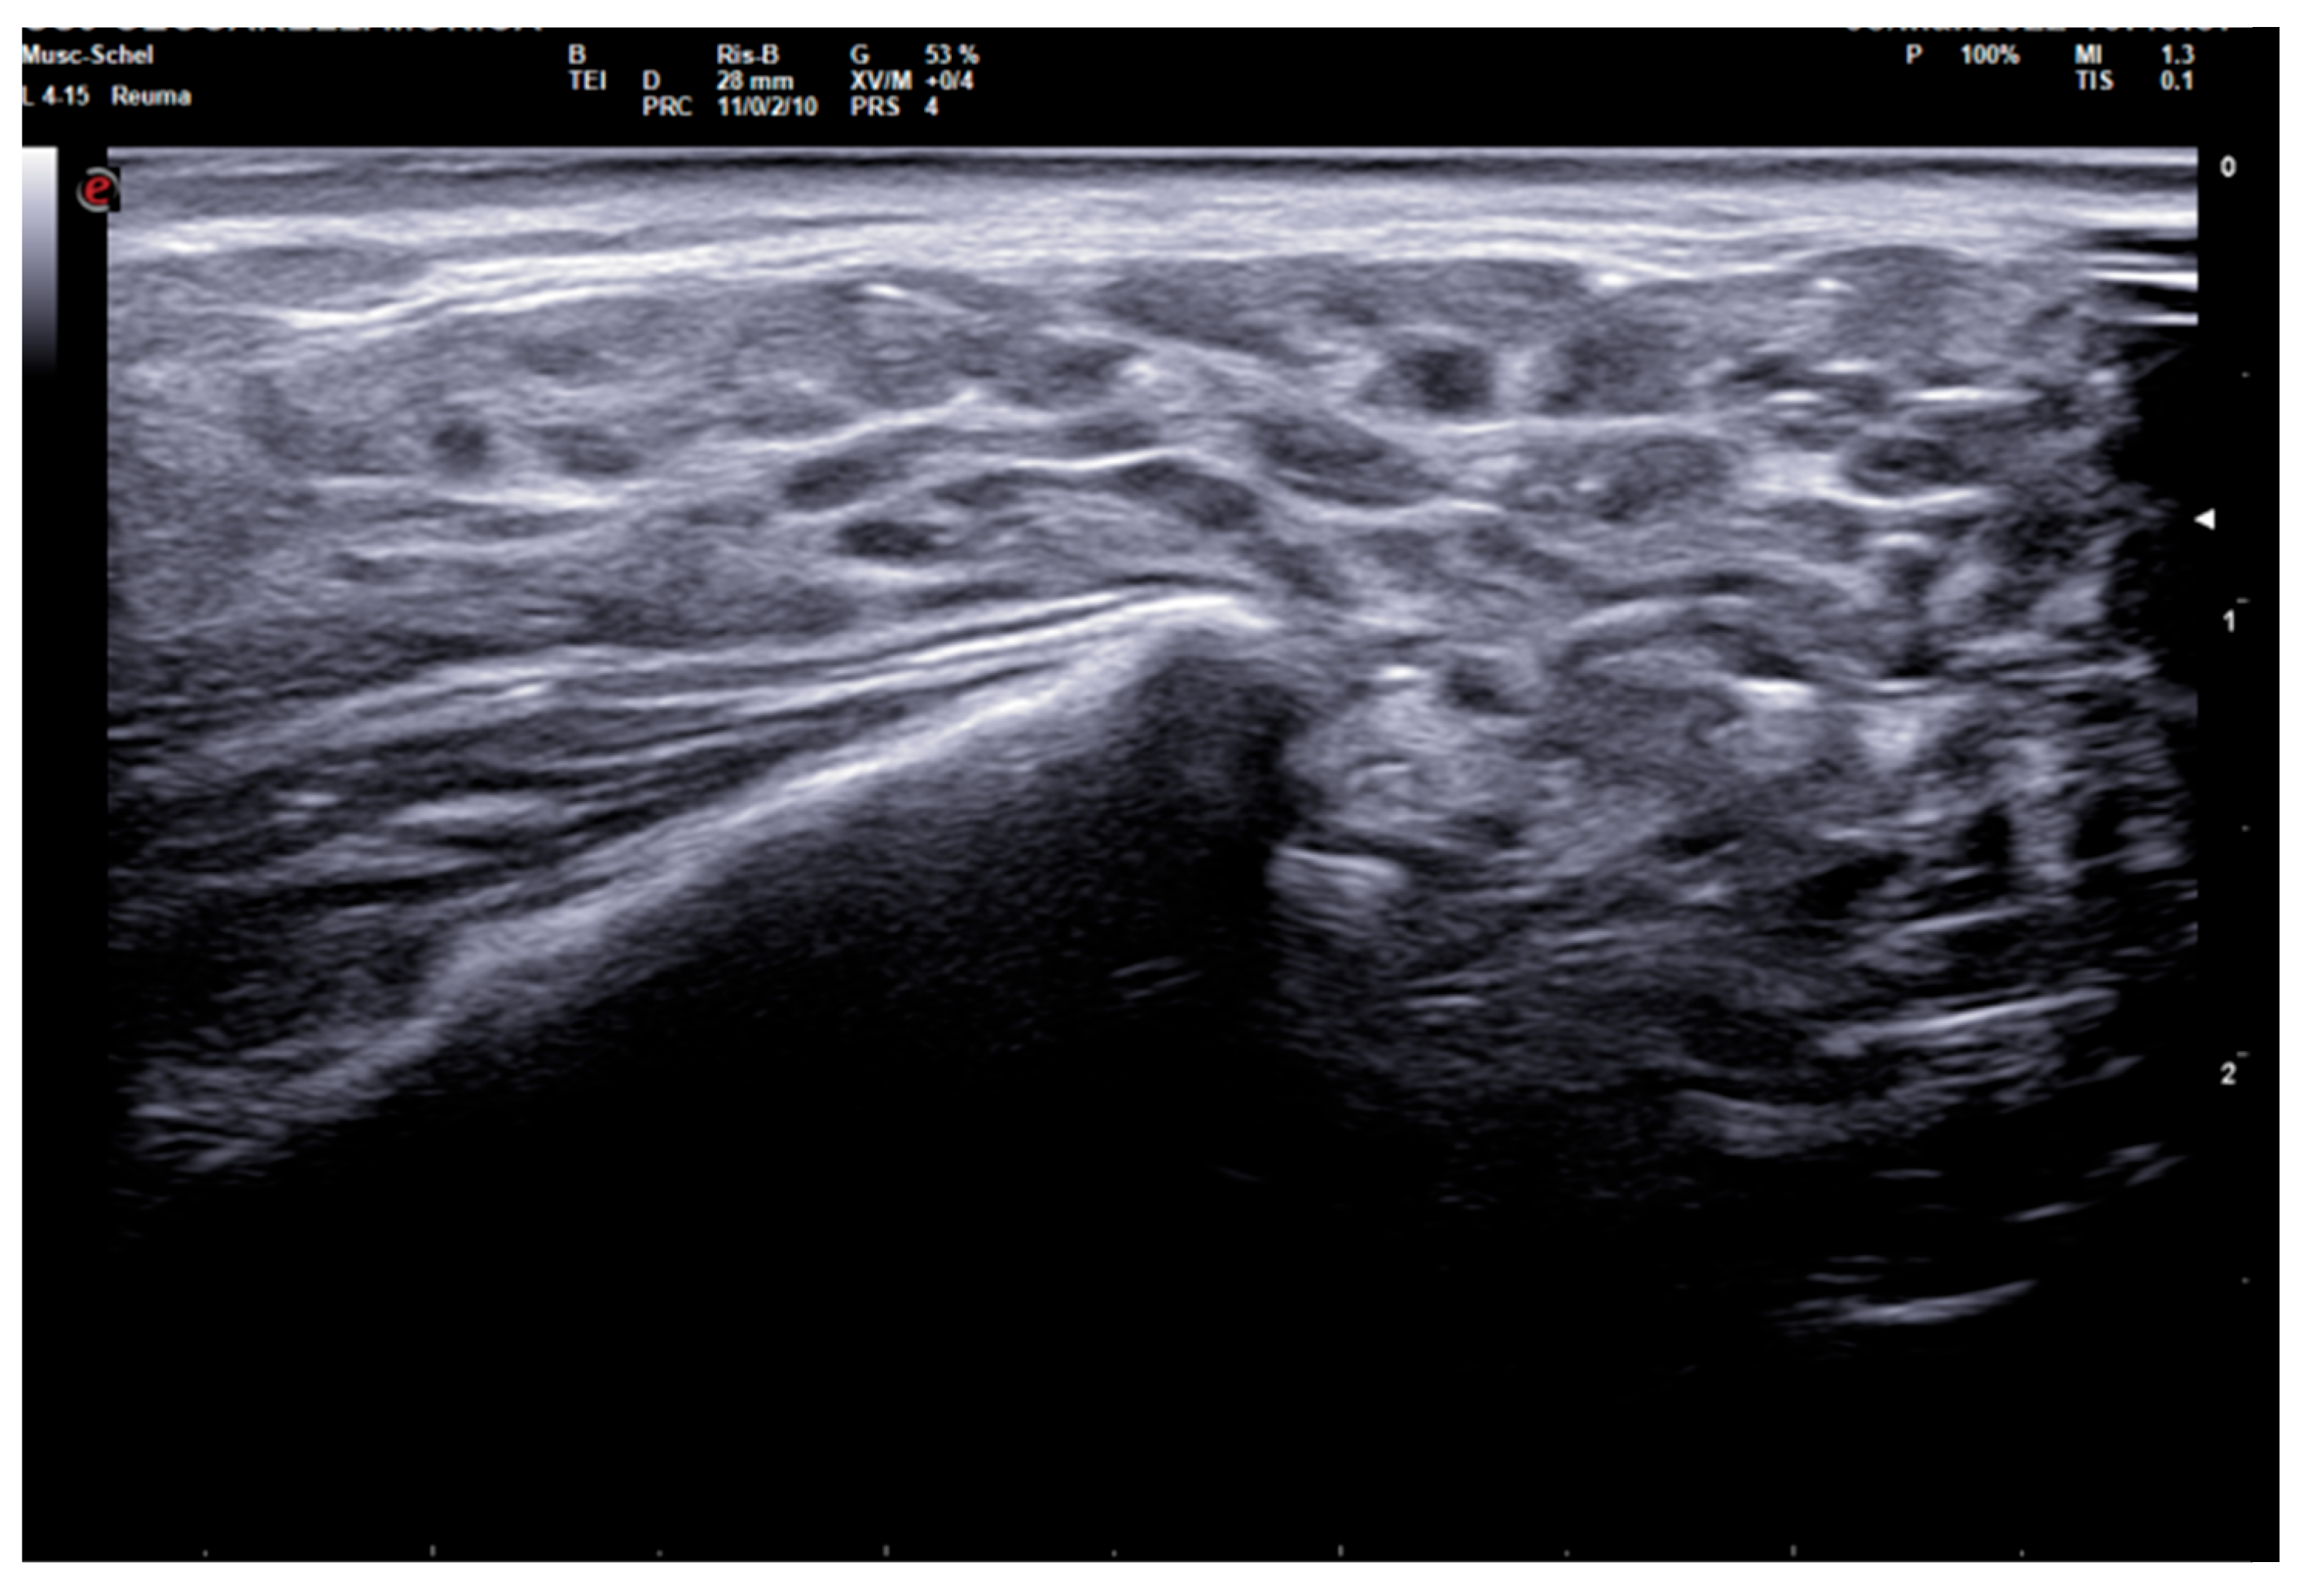

The diagnostic accuracy of the global SGUS score (sum of SGUS scores of all four glands) to diagnose SS was comparable with those of the parotid and submandibular glands on one side. A mild SGUS asymmetry between the two sides can be observed (Figure 5). Moreover, as some patients could have unilateral complaints or show focal glandular enlargement with high risk of lymphoma, a global view of all four glands should be preferred. However, SGUS in only one side might be taken in consideration in the case of previous mono-lateral surgery or radiotherapy without reducing diagnostic accuracy.

This study has several limitations. Specifically, the study was conducted in a context of real clinical practice, so an assessment of intra- and inter-operator agreement is lacking. However, our diagnostic performance data are comparable with previous results [13,14,28]. Due to the same reasons, another limitation is lack of complete immunological data of SS patients. Moreover, no patient was classified as affected from secondary SS, preventing us from evaluating the diagnostic performances of SGUS in this subset. The only patient with peripheral synovitis (see Figure 5) could not be diagnosed with anything other than primary SS. In any case, previous studies demonstrated no significant difference in SGUS appearance between primary and secondary forms of SS [29].

Figure 5. Submandibular glands in seronegative primary Sjogren syndrome. Female 57-year-old patient with peripheral symmetrical synovitis (some proximal inter-phalangeal and metacarpal-phalangeal of hands), sicca syndrome with positive Schirmer test, negative autoimmunity (ANA−, Ro-SSA−, La-SSB−, rheumatoid factor/ACPA−), positive labial biopsy for Sjogren syndrome, and type 1 diabetes mellitus. A coronal oblique scan over submandibular glands (8–24 MHz linear probe) shows a mild asymmetry on SGUS appearance: in the left side (A), moderate inhomogeneity with some hypo-anechoic areas occupying the superficial portion of gland (SGUS-OMERACT score = 2), whereas in the right side (B) SGUS shows mild inhomogeneity of the submandibular gland without hypo-anechoic areas (SGUS-OMERACT score = 1). The SGUS score of parotids was 2 on both sides. In this seronegative patient, only labial biopsy could define Sjogren syndrome diagnosis, but its SGUS global score of 7 had a 100% of specificity for the diagnosis.